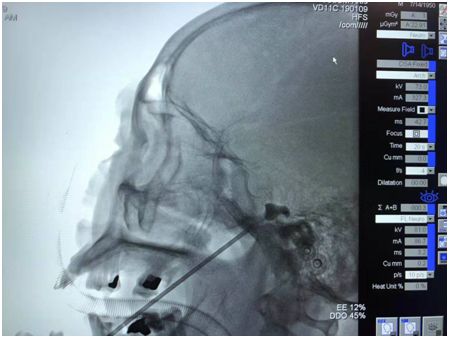

在C形臂引導下經(jīng)嘴角外側(cè)穿刺進入卵圓孔,將球囊導管送至半月神經(jīng)節(jié),充盈球囊,壓迫數(shù)分鐘,破壞神經(jīng)傳導,達到治療目的。

文主任介紹:“根據(jù)劉大爺?shù)牟∏?,按常?guī)的治療思路來說,應該先開顱切除顱內(nèi)腫瘤,再治療三叉神經(jīng)痛。但是他不愿意接受開顱手術,又迫切需要‘止痛’。對于這種想止痛又不愿動刀子的患者來說,通過微創(chuàng)治療三叉神經(jīng)痛便再適合不過了,也就是三叉神經(jīng)微球囊壓迫術。

盡管該患者選擇接受三叉神經(jīng)微球囊壓迫術,但由于病情較特殊,手術較為復雜,難度較大。因為腫瘤長在麥克氏囊,可操作空間小,術中出血幾率高。再者患者年紀大,對手術醫(yī)生來說,是一個不小的挑戰(zhàn)?!?/span>

慶幸的是,劉大爺?shù)氖中g十分成功。文主任表示,劉大爺是自“馬逸教授惠州工作室”成立以來,因此而受益的患者之一。手術取得了令人滿意的成效,術后疼痛完全消失,三叉神經(jīng)痛不復存在;手術創(chuàng)口也僅有一個針眼大小,術畢患者臉上僅見一個創(chuàng)可帖大小輔料,一般2~3天即可出院。